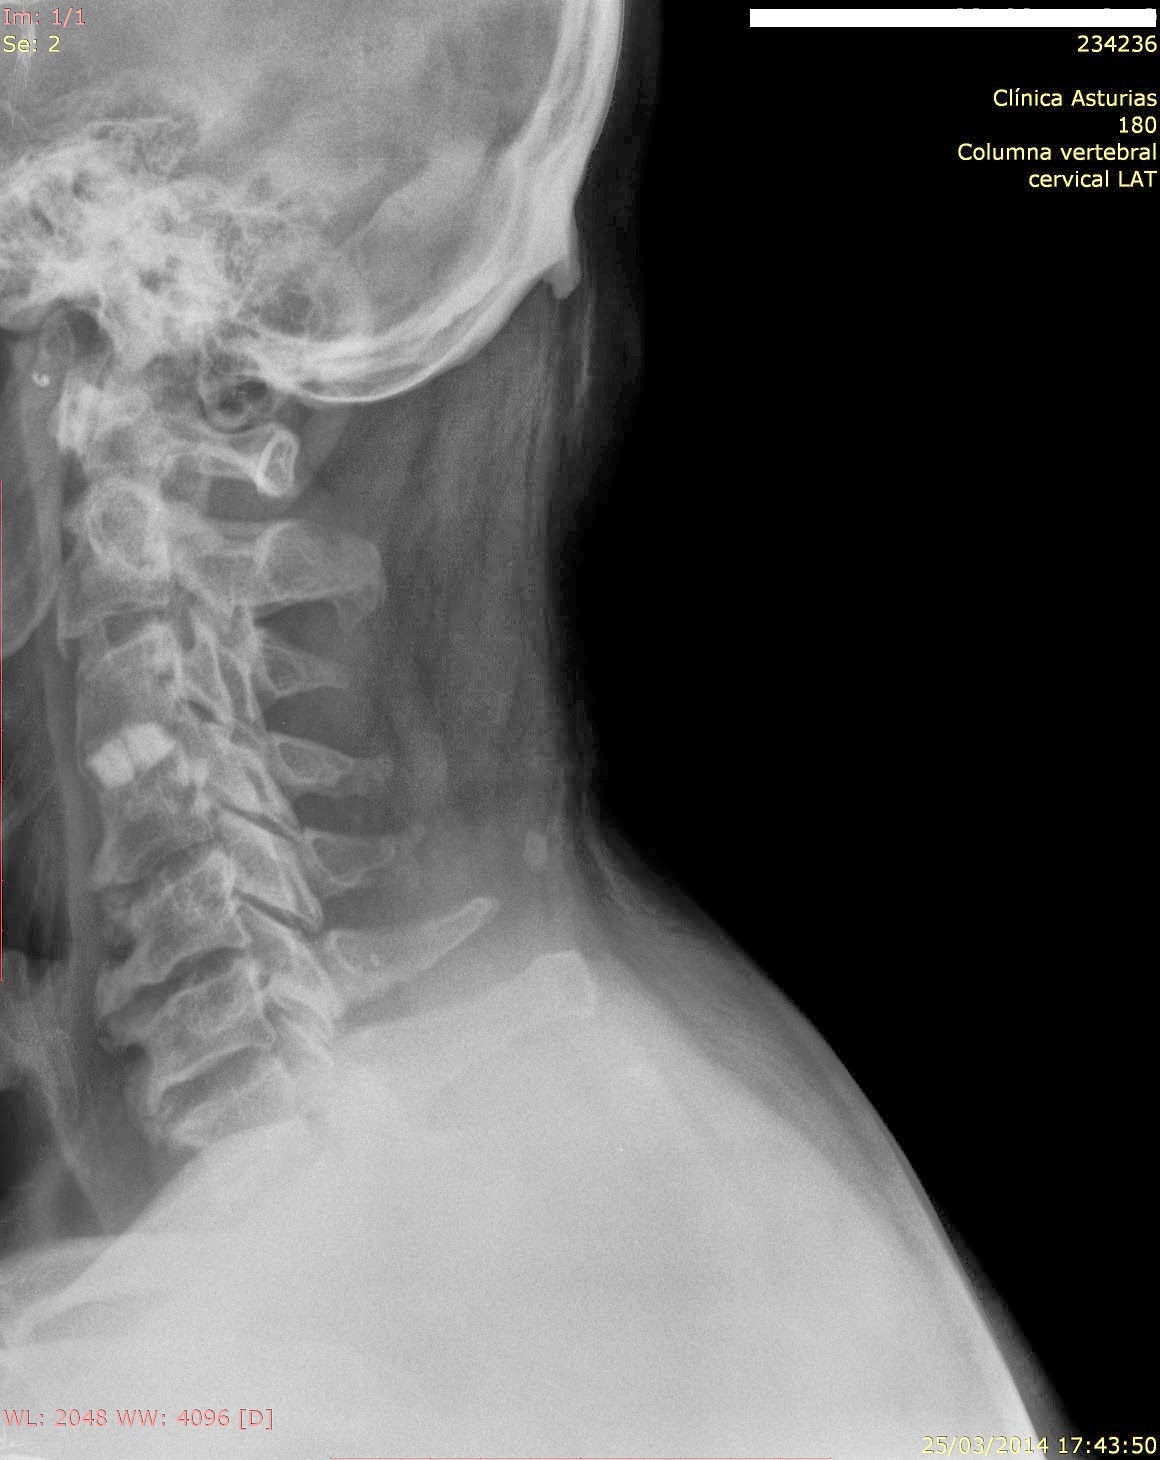

Se me rompió la columna: Artrodesis cervical. Consecuencias.

Source: semerompiolacolumna.blogspot.com